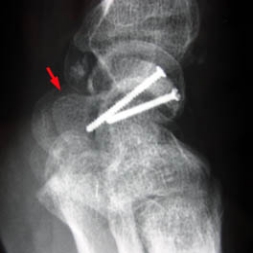

A - Radiographie du poignet de face : Aspect amputé de la tête du capitate (tête de flêche). Ostéosynthèse du scaphoïde. Desalignement luno-triquetral (flêche).

B - Radiographie du poignet de profil : Discèete horizontalisation du scaphoïde. Respect du matériel.

Controle post-opératoire aprés luxation du carpe

(luxation fracture transscaphoidienne, transcapitate rétrolunaire du carpe).